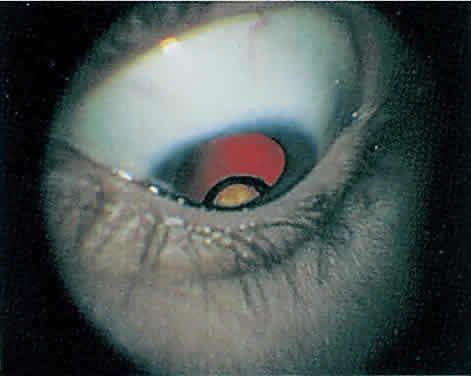

Rhegmatogenous retinal detachment occurs in 10% to 20% of eyes with CMV retinitis.37–39 However, before the AIDS epidemic, there were only five reported cases of this association.10,40 In patients living more than 1 year with CMV retinitis, risk of retinal detachment may be as high as 50%,41 which increases if more than 25% of peripheral retina is involved by disease.41,42 Retinal breaks in eyes with CMV retinitis typically occur within or at the border of necrotic atrophic retina (Fig. 6).43 The ensuing retinal detachments are typically difficult to repair with standard scleral buckling procedures. This is because of the location and number of retinal breaks, the difficulty in visualizing all breaks in necrotic retina, and the high incidence of associated proliferative vitreoretinopathy. In many cases, pars plana vitrectomy and retinal tamponade with silicone oil or long-acting intraocular gas is indicated (Figs. 7 and 8).37,44,45 However, scleral buckling may be considered in small peripheral retinal detachments when the entire involved area can be completely placed on the element. Laser photocoagulation demarcation has also been described to delimit macula-sparing CMV-related retinal detachment.46 Although anatomic success of macular reattachment with surgery is high, the visual results are often limited by the underlying disease process.47 When considering surgical repair of CMV-induced retinal detachment, consideration should be given to the potential for ambulatory vision, the patient's systemic condition and the status of the fellow eye.